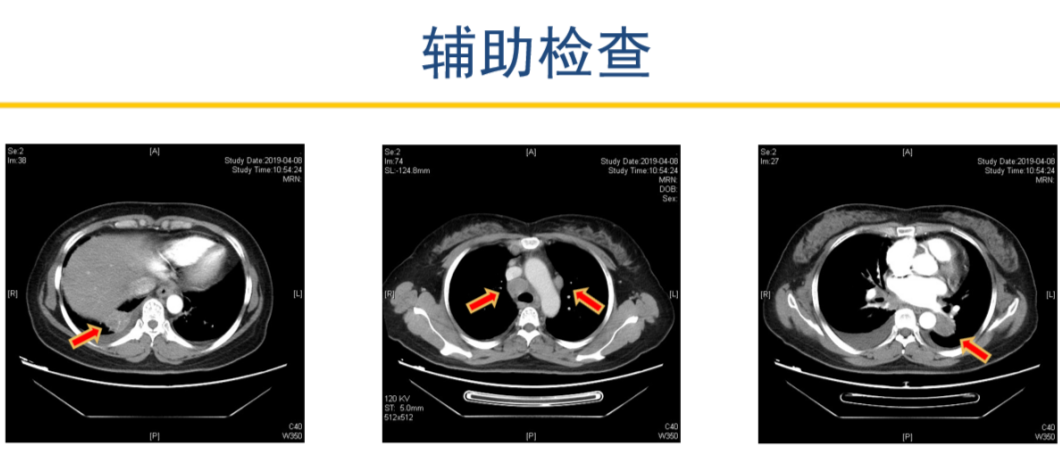

辅助检查情况如下

患者2019-04-08 胸部增强CT,显示左肺下叶占位并纵隔、双肺门、右锁骨上多发肿大淋巴结,考虑肺癌可能。右下肺占位,建议抗炎治疗后复查。